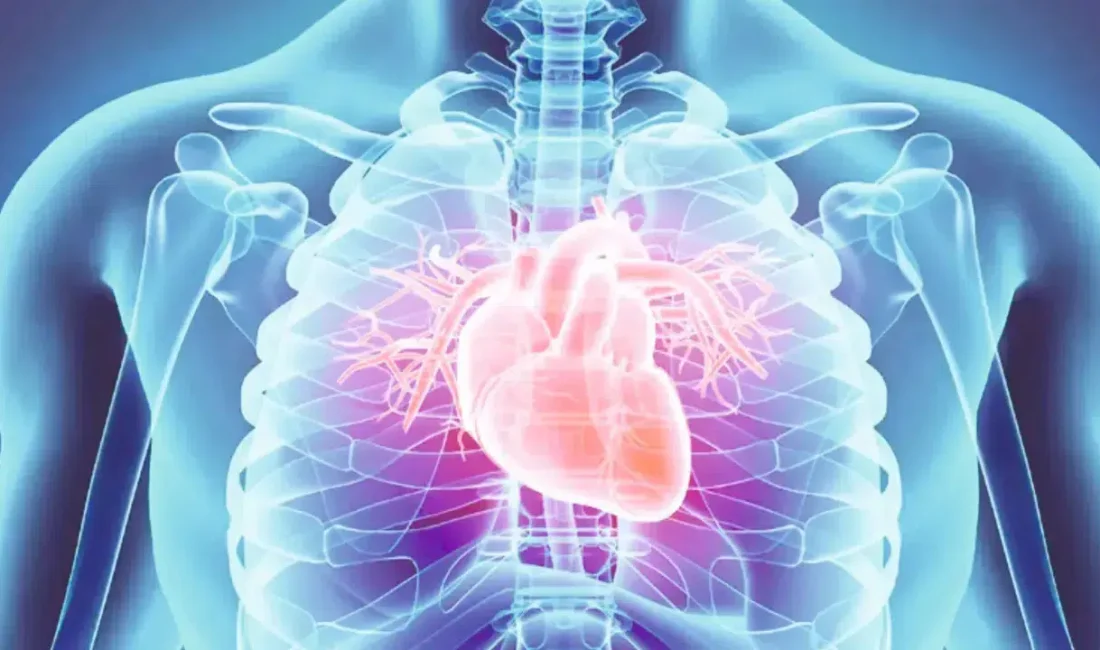

Dünya genelinde her yıl yaklaşık 20 milyon insanın hayatını kaybetmesine neden olan kalp ve damar hastalıkları modern çağın en büyük sağlık tehdidi olmaya devam ederken uzmanlar Türkiye’deki tabloya dair çarpıcı veriler paylaştı.

Kalp ve damar sağlığı, küresel ölçekte en fazla can kaybına yol açan sağlık sorunlarının başında geliyor. Bilimsel veriler, her yıl yaklaşık 20 milyon kişinin bu hastalıklar sebebiyle yaşamını yitirdiğini ortaya koyarken, uzmanlar erken teşhis ve koruyucu önlemlerin hayati önem taşıdığını vurguluyor. Bilecik Eğitim ve Araştırma Hastanesi Kardiyoloji Uzmanı Dr. Öğr. Üyesi Enes Çelik, bu sessiz tehlikeye karşı toplumun bilinçlenmesi gerektiğini belirterek önemli açıklamalarda bulundu.

Ülkemizdeki güncel verileri değerlendiren Dr. Enes Çelik, genç nüfus dahil olmak üzere kalp sağlığının giderek daha fazla tehdit altında olduğunu işaret etti. Yapılan son araştırmaların sonuçlarını paylaşan Çelik, “Ülkemizde, 2023 yılında yapılan bir çalışmada 15 yaş üzerindeki nüfusta kalp ve damar hastalığı sıklığının yüzde 7” ifadelerine yer verdi. Bu oran, milyonlarca vatandaşın doğrudan kalp sağlığı riskleriyle karşı karşıya olduğunu ve her geçen yıl vaka sayılarının artış eğiliminde olduğunu gösteriyor.

Dünya genelindeki 20 milyonluk kayıp rakamı, kalp hastalıklarının sadece bireysel bir sağlık sorunu değil, aynı zamanda küresel bir halk sağlığı krizi olduğunu kanıtlıyor. Uzmanlar; sağlıksız beslenme, hareketsiz yaşam tarzı ve tütün kullanımı gibi faktörlerin bu istatistikleri yukarı çektiğini ifade ediyor. Dr. Öğr. Üyesi Enes Çelik ve kardiyoloji dünyasının önde gelen isimleri, düzenli kontrollerin ve yaşam tarzı değişikliklerinin bu ölümcül tablonun değişmesinde anahtar rol oynayacağının altını çiziyor. Özellikle risk grubundaki bireylerin periyodik taramalardan geçmesi, olası krizlerin önüne geçilmesinde en etkili yöntem olarak kabul ediliyor.